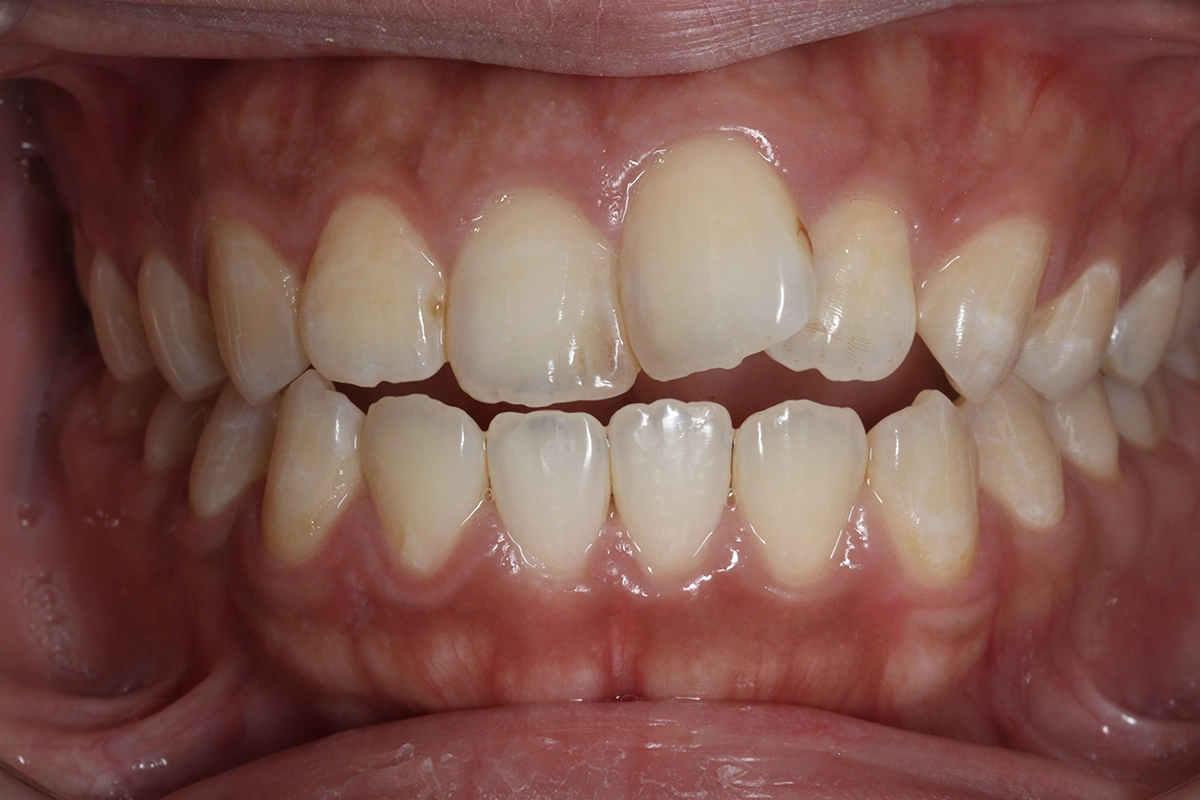

正面

before

奥歯でしっかり噛んでも、上下の前歯が接触せず隙間ができている状態です。前歯で食べ物を噛み切ることができないため、奥歯に過度な負担がかかります。放置すると奥歯の摩耗や顎関節への影響につながることがあります。

開咬(オープンバイト)

上下の前歯がしっかり接触するようになり、前歯で食べ物を噛み切れるようになりました。これにより奥歯への過度な負担も軽減されています。